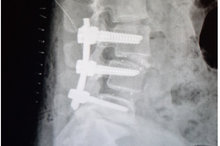

術後腰椎突出改善(童綜合醫院提供)

黃姓婦人經朋友介紹到童綜合醫院微創中心接受治療,副院長徐少克確認患者因體重過重導致腰部支撐力不足,腰椎長期支撐過重之下,導致腰椎第三、第四與第五節椎間盤突出合併脊椎移位;安排住院進行腰椎微創融合手術,術後患者住院5天即出院返家休養,目前大腿麻痛情形改善,也不再受失眠所苦,恢復以前健康時的日常生活作息,因此也願意和家人一同出遊。

徐少克副院長表示,傳統腰椎手術須從腰背正中央進入體內後,切斷腰椎後方兩側肌肉,及切除後脊突及椎板,所以容易造成肌肉組織較大破壞及失血過多,整個脊椎後主樑也被切斷破壞,術後也易產生背肌纖維與萎縮及脊椎無力鄰近節病變等後遺症;腰椎微創融合手術則可以從下背兩側進入腰椎,可以保持肌肉組織完整整個脊椎結構也沒有破壞、術後不需穿笨重的鐵衣,傷口小且失血少,所以術後患者的復原也較快和不痛,大多是5天內即可出院,讓患者能提早返回工作崗位與恢復正常生活。